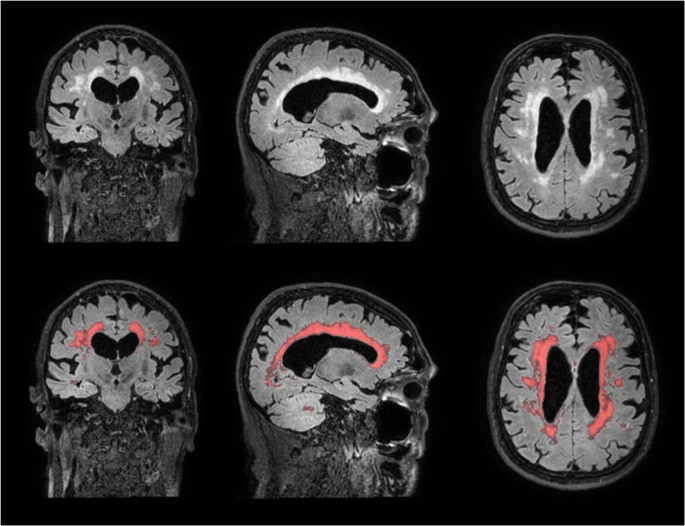

Example Of Small Vessel Disease Progression On Brain Mri Figures Show Download Scientific Diagram